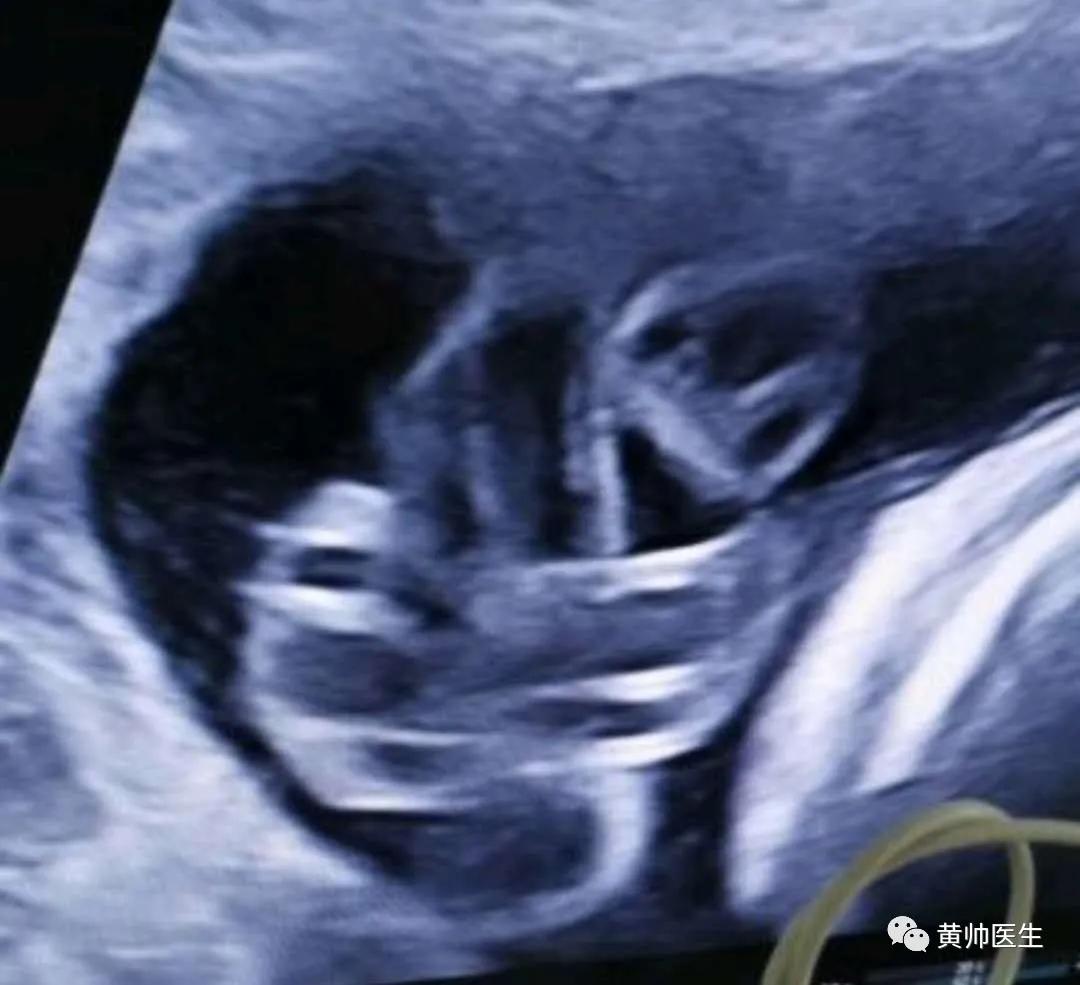

孕妈林某,来院行常规检查,胎心监护检查没有确切异常,孕妈来找黄帅医生行超声检查,评估胎儿大小和宫内情况,检查后指标都很好,脐带绕颈一圈,其他没有特殊,偶都准备让病人起床了,突然惊呼一声“等一哈!”,仔细一看,缠绕在颈部的脐带有点异常,哪里不对呢?只见一堆血管绞在那里,超声如图:

(超声下的脐带图)

是不是有点不对,脐带向上走形后又向下走,然后绕到自己的前方,然后缠住自己到自己的后方后从最开始的峰下方钻出来。

脐带真结的超声表现描述类似于四叶草,但这种图形无特异性,而且也可见于脐带假结或排列紧密的脐带环。

另一个超声特征为“悬挂的套索”,当被紧密围绕时可从横截面图像上观察。

应用彩色多普勒超声,尤其是三维能量多普勒成像,可为疑似诊断提供支持。